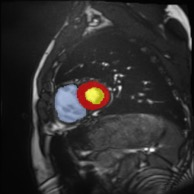

Medical data often exhibits long-tail distributions with heavy class imbalance, which naturally leads to difficulty in classifying the minority classes (i.e., boundary regions or rare objects). Recent work has significantly improved semi-supervised medical image segmentation in long-tailed scenarios by equipping them with unsupervised contrastive criteria. However, it remains unclear how well they will perform in the labeled portion of data where class distribution is also highly imbalanced. In this work, we present ACTION++, an improved contrastive learning framework with adaptive anatomical contrast for semi-supervised medical segmentation. Specifically, we propose an adaptive supervised contrastive loss, where we first compute the optimal locations of class centers uniformly distributed on the embedding space (i.e., off-line), and then perform online contrastive matching training by encouraging different class features to adaptively match these distinct and uniformly distributed class centers. Moreover, we argue that blindly adopting a constant temperature $\tau$ in the contrastive loss on long-tailed medical data is not optimal, and propose to use a dynamic $\tau$ via a simple cosine schedule to yield better separation between majority and minority classes. Empirically, we evaluate ACTION++ on ACDC and LA benchmarks and show that it achieves state-of-the-art across two semi-supervised settings. Theoretically, we analyze the performance of adaptive anatomical contrast and confirm its superiority in label efficiency.

翻译:医学数据经常呈现长尾分布和重度类别不平衡,这自然导致在对少数类别(即边界区域或罕见目标)进行分类时出现困难。最近的研究在长尾情况下通过装备医学影像的无监督对比标准,明显改进了半监督医学图像分割。然而,在标记的数据部分中,类别分布也极为不平衡,因此它们的表现如何仍不清楚。在本研究中,我们介绍一种采用自适应解剖对比度改进的对半监督医学分割行动的框架(ACTION++)。具体来说,我们提出了一种自适应监督对比损失,它首先在嵌入空间上计算出不同类别的优化位置(即离线),然后通过鼓励不同类别之间的特征与这些不同和均匀分布的类别中心相适应的在线对比匹配训练来进行自适应匹配。此外,我们认为,在长尾医疗数据中盲目采用常温度$\tau$不是最优的,因此通过一个简单的余弦计划来使用动态$\tau$来产生更好的多数类别和少数类别之间的分离。在实证方面,我们在ACDC和LA基准测试中评估ACTION++,并展示了其在两种半监督设置下的最新成果。从理论上讲,我们分析了自适应解剖对比度的性能,并证实了它在标签效率上的优越性。